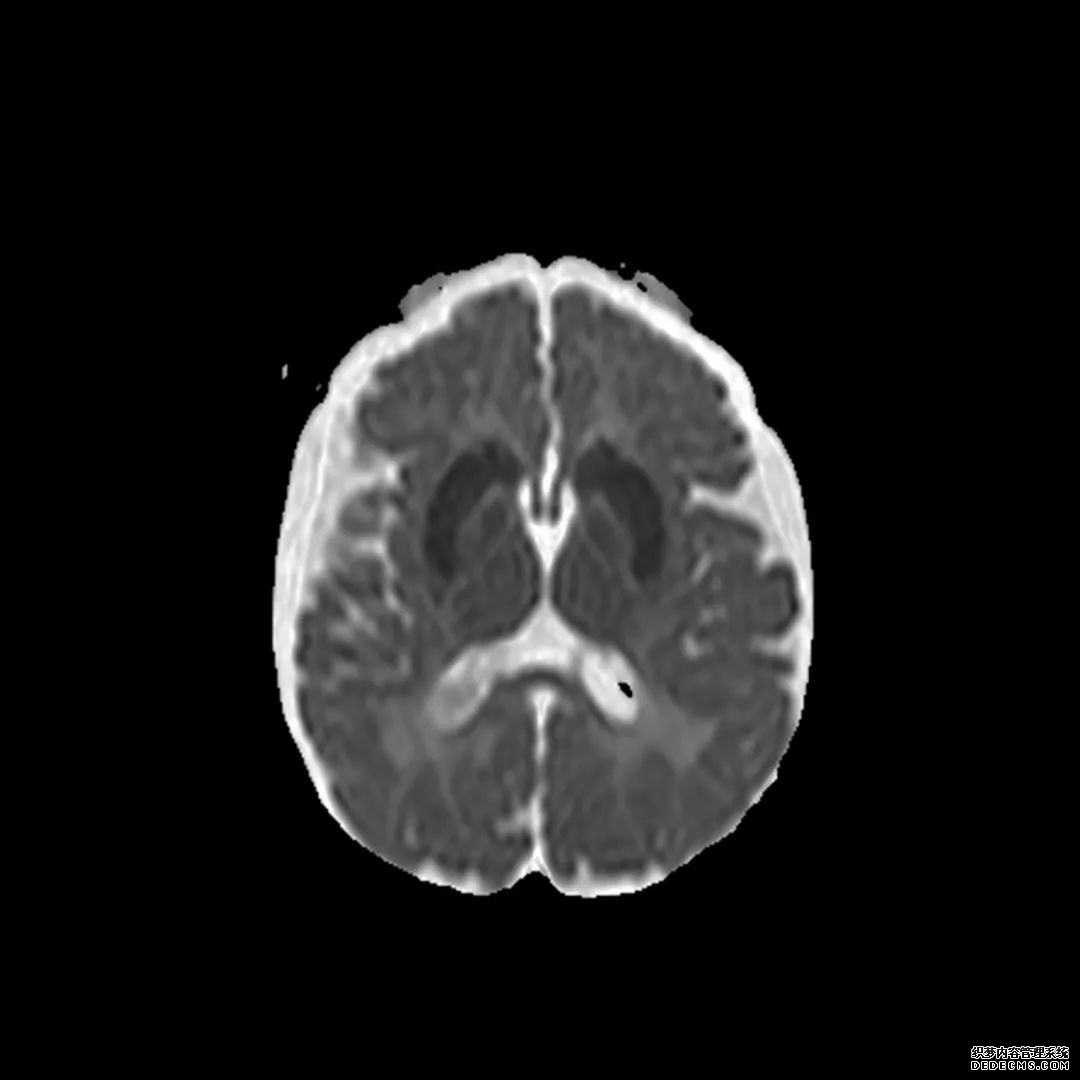

脑部CT检查显示扁豆状核内有略对称的低密度区。

脑MRI显示尾状核、扁豆状核和脑梗头部T2/FLAIR呈双侧对称异常高信号。扩散限制涉及这些区域,其特征是扩散加权DWI(B-1000)上的高强度,ADC图上相应的减弱强度。